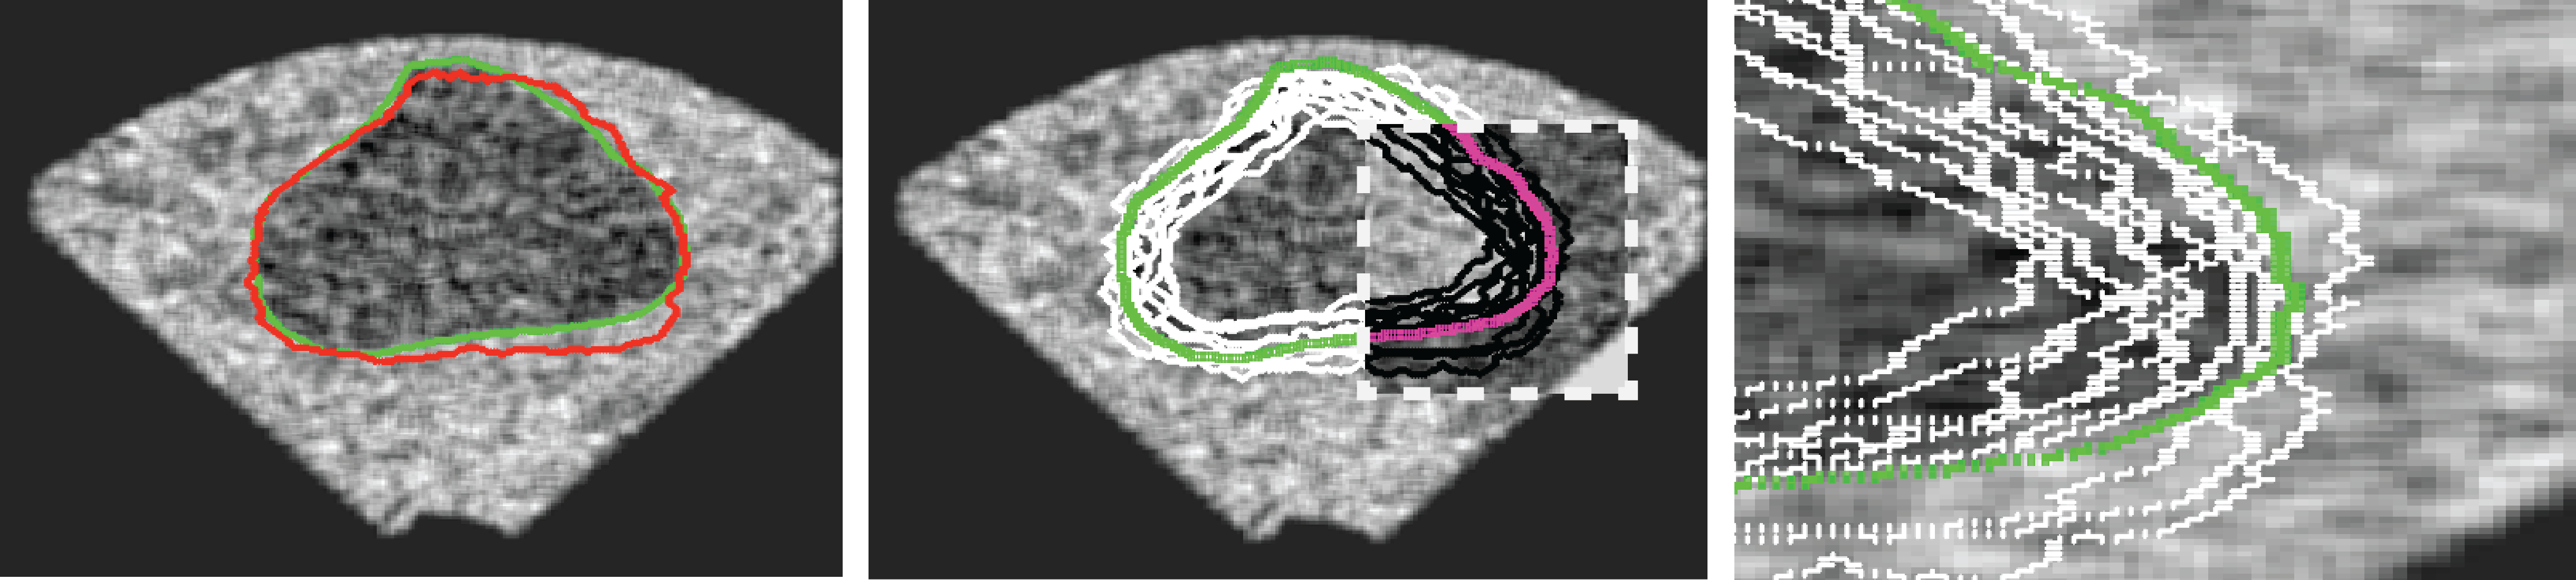

One can show that and , hence . It is obvious that can come from an algorithm in which case is the ground-truth from one or multiple users. As well, can be manual delineation by an expert whereas is then gold standard as consensus among multiple experts. For instance, when segmenting the prostate gland, one has to actually pay more attention to some specific zones such as the rectal wall, neurovascular bundle and urethral sphincter (Figure 2, left). In many cases, a segment may have a large overlap with the ground-truth but may not be accurate enough in significant zones (Fig. 2, right). The accuracy of such segments should be penalized according to the zonal accuracy.

Mapping instead of Registration (Algorithm 3) – Finding the correspondent pixels in and consequently in , given the zonal coordinates in , seems to be a typical “registration” task. However, based on our experimental results we decided to not use registration algorithms for this purpose. The non-rigid registrations we tested were both time-consuming (which may not be a critical drawback) and inaccurate. Whereas one may use a specific registration algorithm in context of a familiar segmentation task, we do provide a quasi-non-rigid mapping procedure that is very fast, due to its simplicity, and can handle small irregularities quite easily. For this, first we do fix some points on the contour of the master gold (see Algorithm 4 in Appendix) and then map them to the ground-truth (see Algorithm 5 in Appendix) and segment (Algorithm 3; see Figure 3).

We generated 500 images from their corresponding gold-standard images111All images and their segments are available online: http://tizhoosh.uwaterloo.ca/. Furthermore, we generated 20 different segments for each image, assuming that there were 20 users. Figure 4 shows five examples of real and synthetic TRUS images. One should bear in mind that the purpose here was not to simulate the images realistically, but rather to have a base from which to generate variable segments from a perfect segment. Figure 5 shows an example of the gold segments and simulated user contours. The variability, coupled with the gold segment, is what is needed in our experiments.